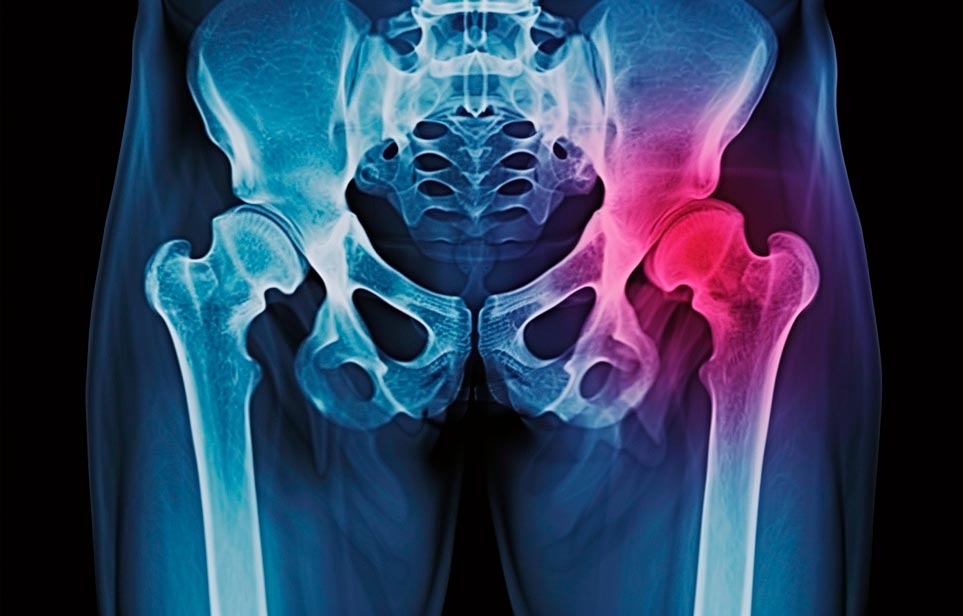

Эффективная и профессиональная реабилитация после перелома шейки бедра в Черноморском осуществляется по демократичным ценам лучшими специалистами современной медицинской клиники «Заботливые люди» с применением персонального подхода к каждому пожилому человеку с такой тяжёлой травмой бедренной кости ноги. В процессе осуществления такой специализированной услуги все наши пациенты имеют возможность получения качественного и достойного обслуживания, эффективного восстановления. Лучший дом престарелых позаботиться о Вашем близком человеке.

Такая травма в большей части случаев возникает у граждан преклонного возраста. При её появлении на протяжении длительного времени сохраняются болевые и неприятные ощущения в области паха, при которых серьёзно ухудшается качество жизни, возникает множество последствий для его жизни и здоровья.

По какой симптоматике можно определить перелом шейки бедра?

Выявить его можно по возникновению следующей тревожной симптоматики:

- Визуально повреждённая нога сокращается на несколько сантиметром из-за сокращения мышц.

- Стопа выворачивается наружу.

- В лежачем положении человек не может поднять ногу.

При такой симптоматике важно незамедлительно обращаться к специалистам для получения всей необходимой помощи, терапии и восстановления после перелома шейки бедра. Если не оказать помощи старику, то это приведёт к гноению, инвалидности, иным видам осложнений.